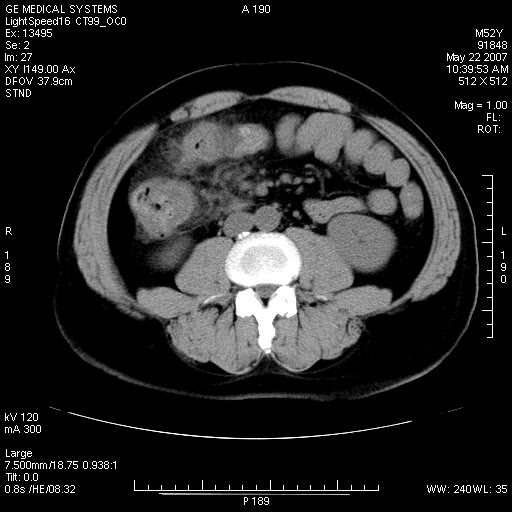

以下是引用余辉在2007-5-22 20:12:00的发言:[br]升结肠管壁明显增厚,增强有静脉期持续增强,结合患者病史,考虑结肠癌可能性大,临近脂肪影密度增高,混浊,恐有肠系膜浸润转移,建议镜检

以下是引用dyqct在2007-5-22 20:43:00的发言:[br]支持结肠肝曲占位性病变(浸润型结肠癌可能性大)。胆总管下端扩张,原因待查。

以下是引用gaoxiao在2007-5-22 20:49:00的发言:[br]考虑升结肠癌向周围侵犯,胰头钩突受侵。